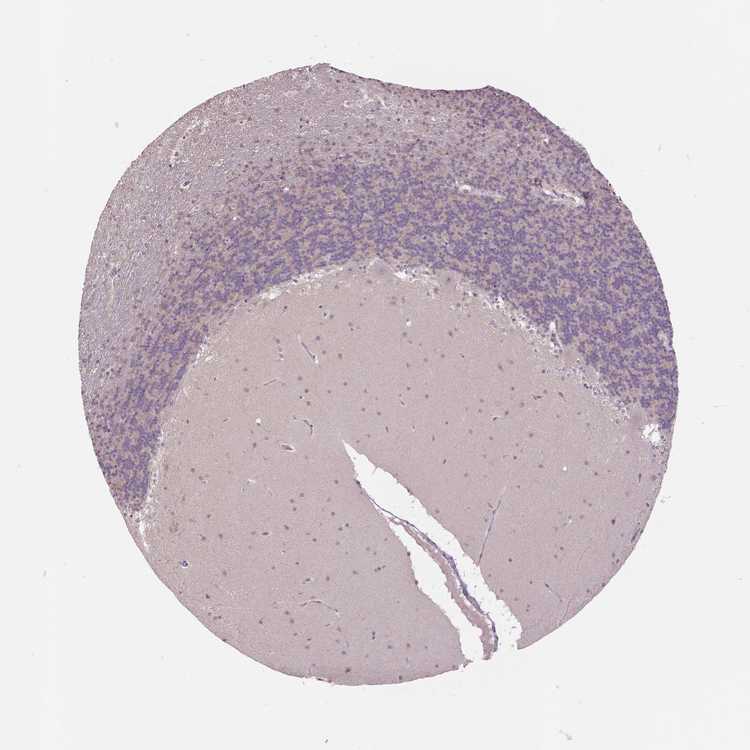

BRAIN CEREBELLUM Show tissue menu

CEREBELLUM - Expression summary

CEREBELLUM - Antibody stainingi

Antibody staining in the annotated cell types in the current human tissue is reported as not detected, low, medium, or high, based on conventional immunohistochemistry profiling in selected tissues. This score is based on the combination of the staining intensity and fraction of stained cells.

Each image is clickable and will lead to virtual microscopy that enables deeper exploration of all samples and also displays staining intensity scores, fraction scores and subcellular localization as well as patient and tissue information for each sample.

Antibody HPA057684

Purkinje cells Not detected

Cells in granular layer Low

Cells in molecular layer Not detected